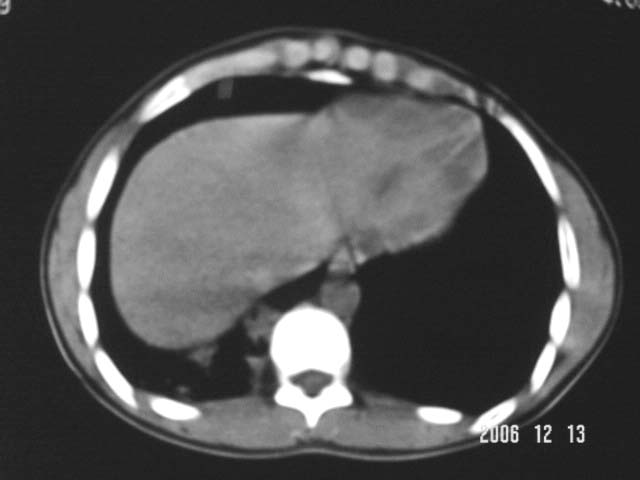

标题: CT5614:外伤病人男,20岁,右上腹痛.余肺野(-) [打印本页]

标题: CT5614:外伤病人男,20岁,右上腹痛.余肺野(-)

外伤病人男,20岁,右上腹痛,ct显示:右肺下叶后基地段见斑片状高密度影,密度不均,边界清,考虑1,右肺下叶肺挫伤;2,炎症。